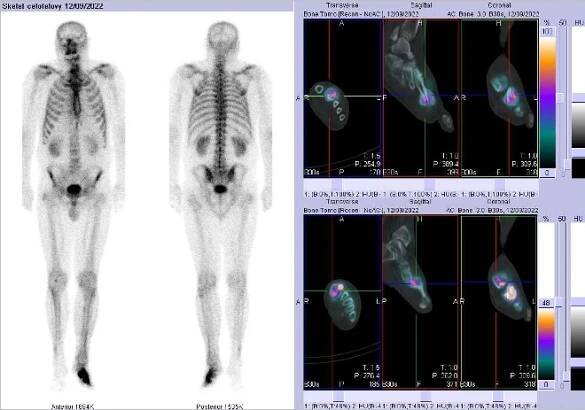

Obr.č.2: Celotělová scintigrafie a fúze obrazů SPECT a CT.  Zaměřeno na ložisko v levé noze.